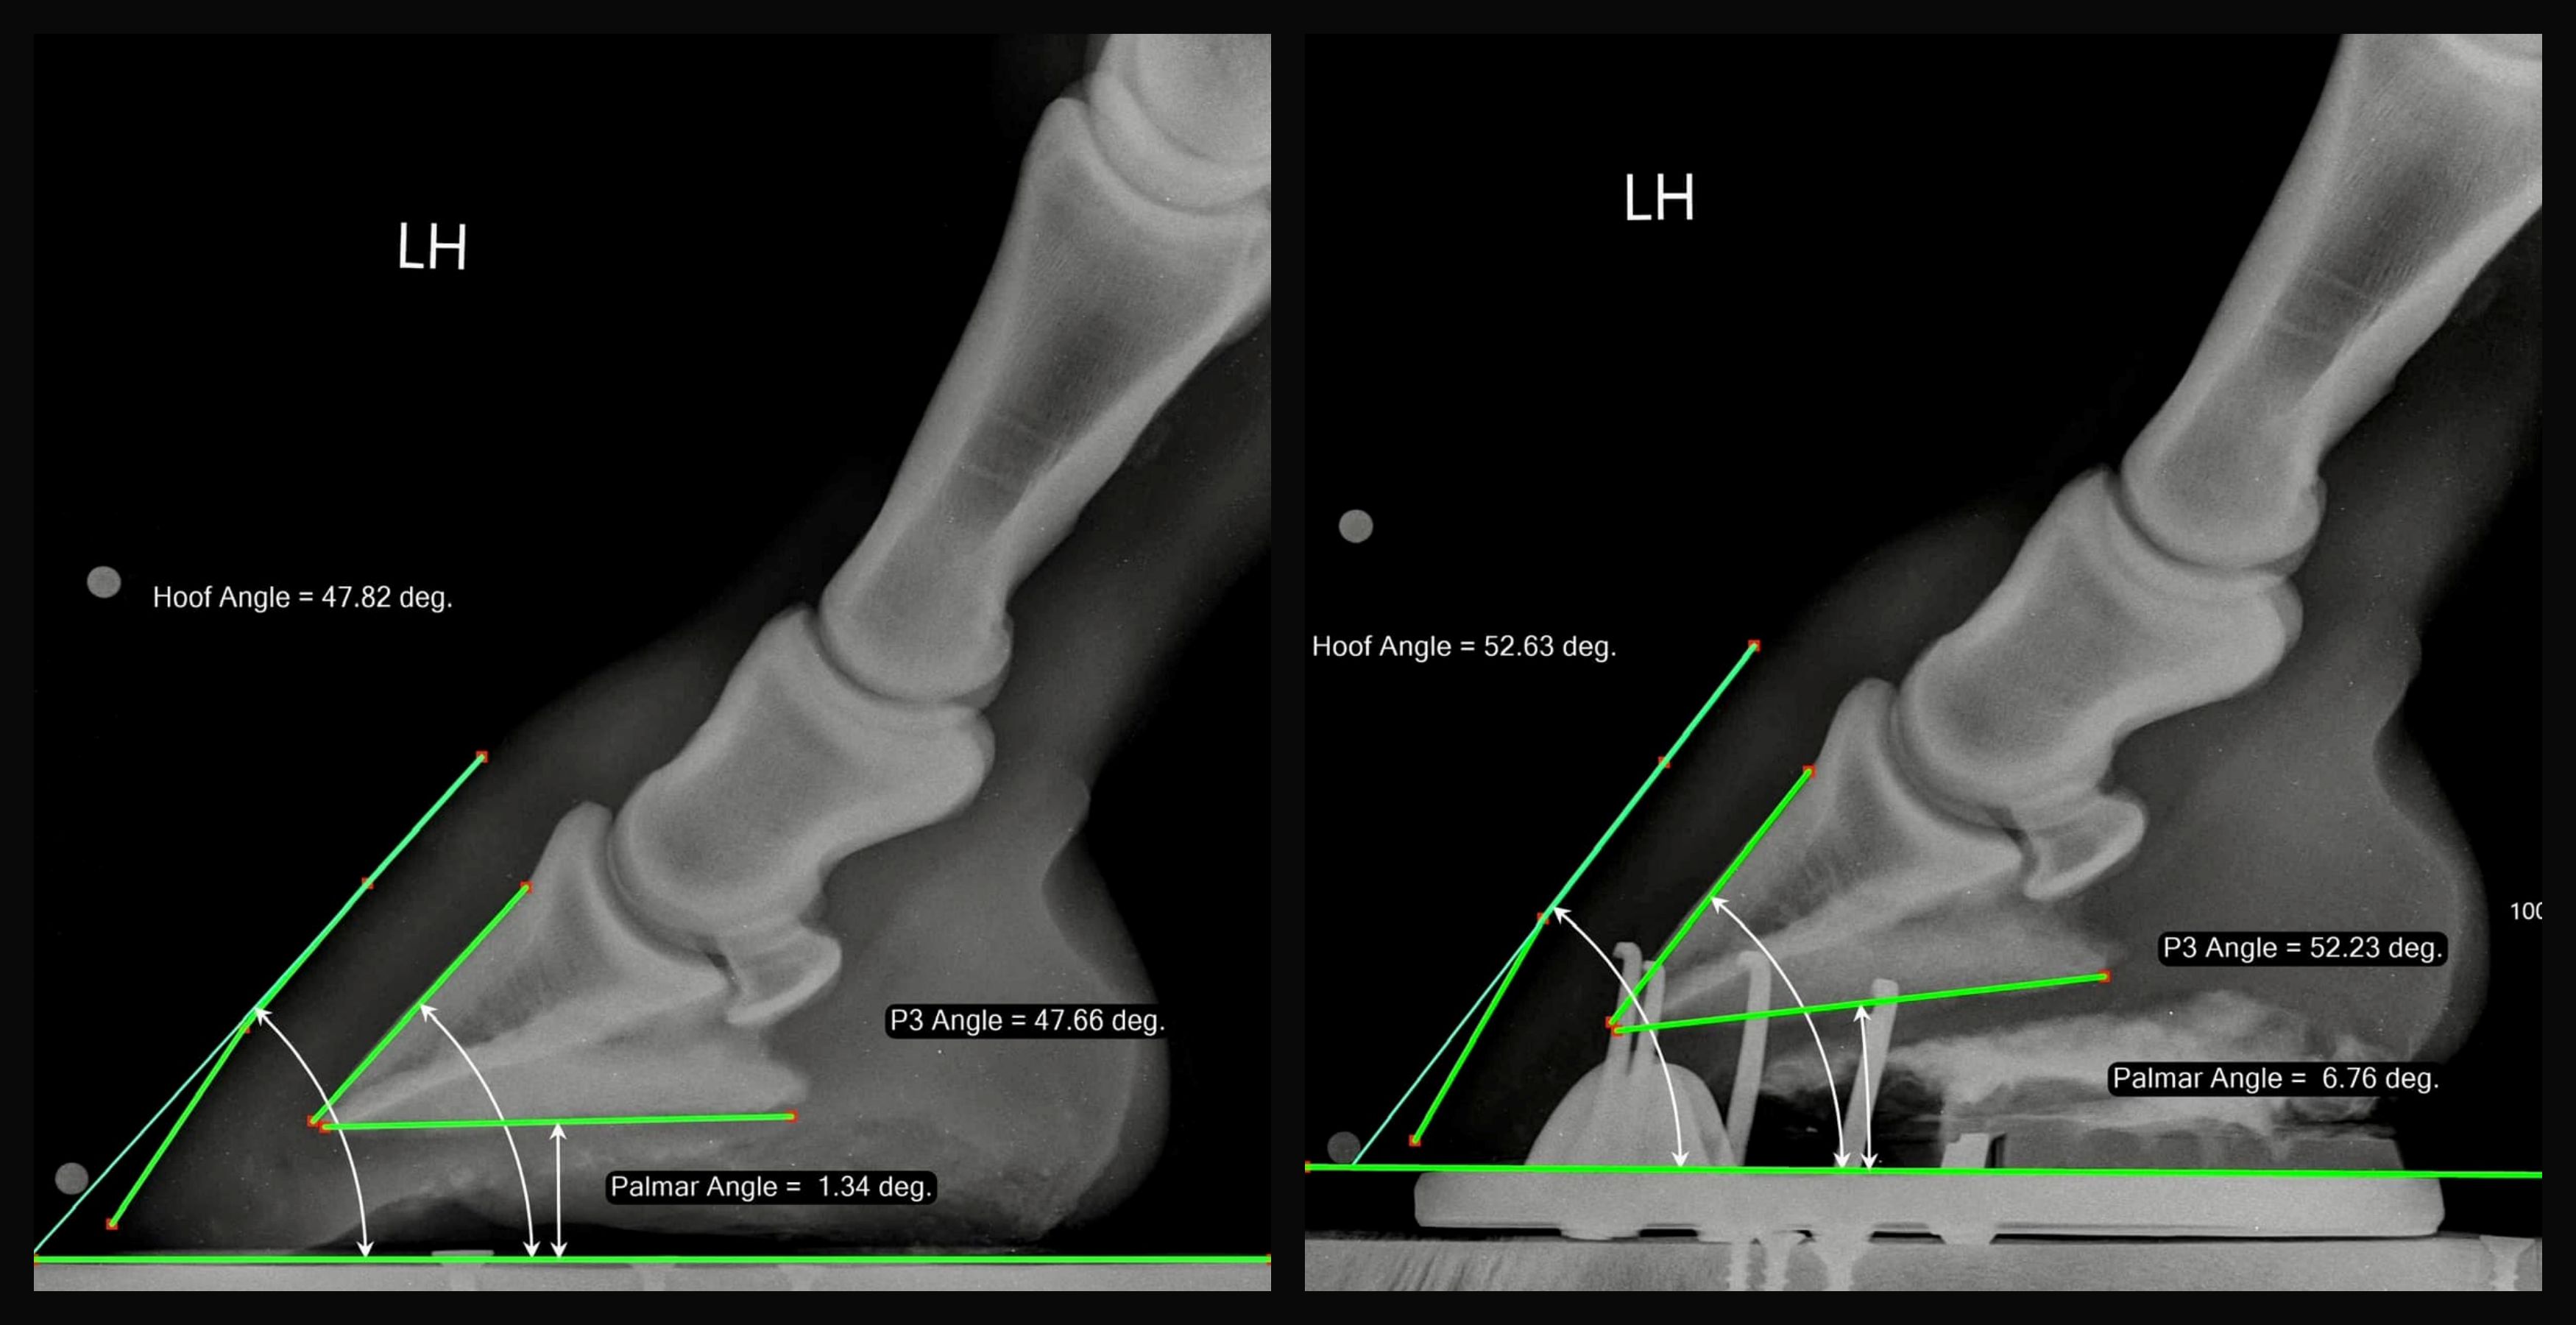

Hovbenets vinkel före och efter en korrigande skoning 👇

*Photocredit to Wayne Turner - Progressive Equine Services - Australia

I hovslagaren Yogi Sharps egen studie av hästar med NPLA så berättar han i ett Facebookinlägg att han såg samma mönster: kronrandsvinkeln på bakhovar låg oftast runt 29–30 grader på den typen av hästar med negativt vinklat hovben. När den plantara vinkeln (hovbenets vinkel) i hoven korrigerades upp med hjälp av terapeutisk hovvård, förändrades även kronrandsvinkeln och hamnade då runt 23 grader. Hos en genomsnittlig häst, när hoven är korrekt balanserad, pekar denna vinkel fram mot främre karpus.(framknät)